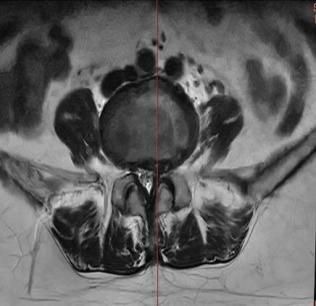

• 不同入路脊柱内镜手术治疗L4/5节段脱垂型腰椎间盘突出症的疗效比较

摘要:目的 观察经椎间孔入路内镜下腰椎间盘切除术(TELD)和经椎板间入路内镜下腰椎间盘摘除术(IELD)治疗L4/5节段脱垂型腰椎间盘突出症(LDH)的临床疗效。方法 回顾性分析2020年11月-2022年11月该院采用脊柱内镜手术治疗的75例L4/5节段脱垂型LDH患者的临床资料。根据手术入路的不同,将患者分为TELD组(53例)和IELD组(22例)。比较两组患者的手术情况和术后疗效。结果 与TELD组比较,IELD组的手术时间明显缩短,术中透视次数明显减少,差异均有统计学意义(P < 0.05);两组患者住院时间和并发症发生率比较,差异均无统计学意义(P > 0.05)。所有患者术后均获得12~19个月的随访。两组患者末次随访时的视觉模拟评分法(VAS)评分和Oswestry功能障碍指数(ODI)明显低于术前,且IELD组明显低于TELD组,差异均有统计学意义(P < 0.05)。按照突出物和神经根的不同位置进一步分析,两组肩上型患者(TELD组10例,IELD组6例)末次随访时的VAS评分和ODI明显低于术前,且IELD组末次随访时的VAS评分明显低于TELD组,差异均有统计学意义(P < 0.05);两组腋下型患者(TELD组8例,IELD组16例)末次随访时的VAS评分和ODI明显低于术前,且IELD组明显低于TELD组,差异均有统计学意义(P < 0.05);35例肩前型患者经TELD术后,末次随访时的VAS评分和ODI明显低于术前,差异有统计学意义(P < 0.05)。按照突出物的不同Lee分区进一步分析,两组Lee Ⅲ区患者(TELD组44例,IELD组10例)末次随访时的VAS评分和ODI明显低于术前,且IELD组的ODI明显低于TELD组,差异均有统计学意义(P < 0.05);两组Lee Ⅳ区患者(TELD组9例,IELD组12例)末次随访时的VAS评分和ODI明显低于术前,且IELD组明显低于TELD组,差异均有统计学意义(P < 0.05)。结论 采用TELD和IELD治疗L4/5节段脱垂型LDH,均可获得较满意的减压效果,但IELD的手术时间相对较短,X线透视次数较少,且对肩上型、腋下型、Lee Ⅲ区和Lee Ⅳ区的减压效果更有优势。